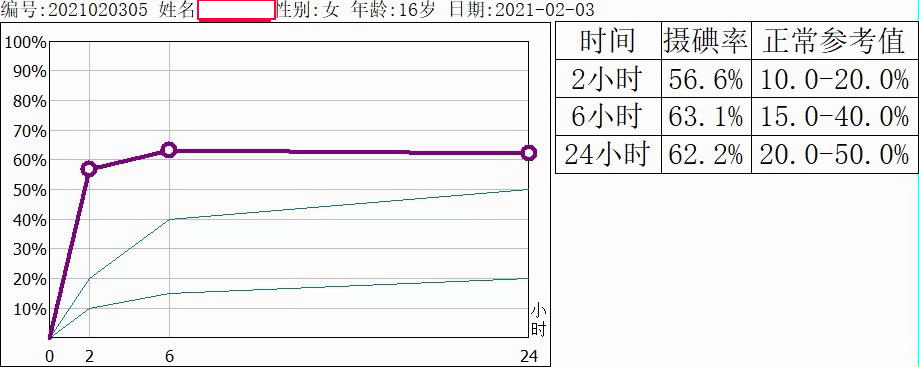

苏州九院核医学科现有GE OPTIMA640型SPECT/CT仪一台,可以常规开展单光子核素显像,如肾脏动态显像、骨显像、脑血流灌注显像、心肌血流灌注显像、唾液腺显像、甲状腺显像、甲状旁腺显像、肾上腺髓质显像、淋巴显像、消化道出血显像、肝胆动态显像、异位胃黏膜显像等检查,为临床疾病诊断和治疗提供帮助。有JXY-Ⅱ型甲状腺摄碘功能测量仪一台,用于检测甲状腺组织对碘的摄取能力和碘在甲状腺组织中的有效半衰期,为甲状腺疾病诊疗提供依据。